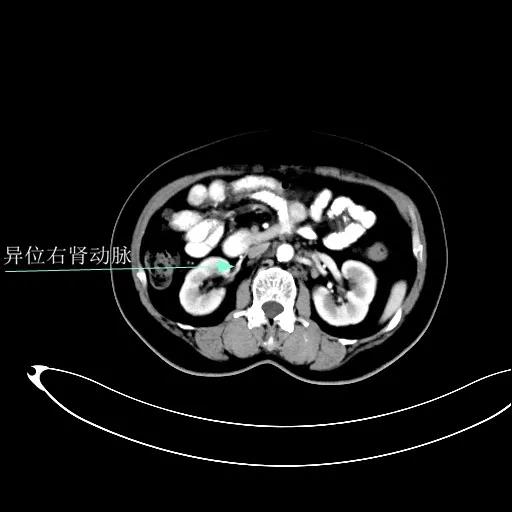

某患者因为“腹痛1周”而入院,外院B超提示子宫上方囊实性肿物,CT提示:左侧附件区占位,并盆腔及腹主动脉旁淋巴结转移。右肾动脉有右肾动脉及异位右肾动脉,其下均有肿大淋巴结。

肾血管总体变异率为35%左右,左侧型发生率为7.5%-23.5%,右侧型发生率为10%-25.3%,双侧型发生率为5.7%。肾动脉一般走行于肾静脉后方。本例异位右肾动脉由腹主动脉发出,经肾静脉前方走行进入右侧肾门,因此称为异位右肾动脉。不论哪个肾动脉分支,均为肾脏相应区域的终末供血动脉,如果发生病变或手术损伤,即可造成相应区域的缺血坏死,因此肾动静脉下淋巴结切除术过程中需警惕异位肾动脉或副肾动脉的存在。